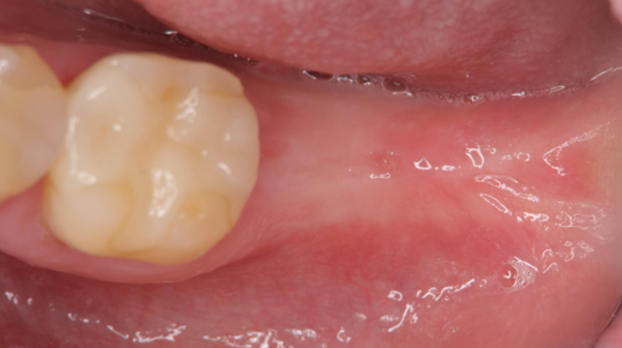

3. During the implant placement, a certain degree of bone and soft tissue deficiency was identified in the edentulous area. Consequently, bone graft (0.25g) and a collagen membrane were simultaneously placed.

Bone and soft tissue deficiency in the edentulous area